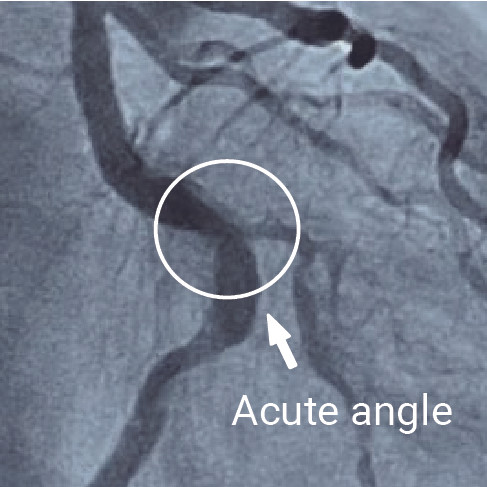

Angiography showed a moderate stenosis (50 - 60%) of the left circumflex artery (LCX) with tortuosity (Fig. 1, 2)

In our Cath Lab, we have three different options to measure FFR, the other two are wire-based. Specifically looking at the characteristics of this angled artery, considering the well-known low navigability of a pressure wire, we saw that the TruePhysio® pressure microcatheter was the best option because we were able to use our workhorse wire and placed the microcatheter over it.

TruePhysio® pressure microcatheter could easily pass the anatomy with an acute angle only in seconds which would take a pressure wire to perform in 10-15 minutes.